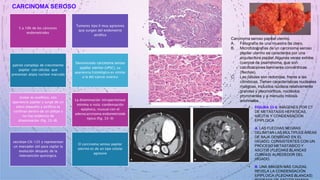

CARCINOMA SEROSO

5 a 10% de los cánceres

endometriales

Tumores tipo II muy agresivos

que surgen del endometrio

atrófico

patrón complejo de crecimiento

papilar con células que

presentan atipia nuclear marcada

Denominado carcinoma seroso

papilar uterino (UPSC), su

apariencia histológica es similar

a la del cáncer ovárico

tumor es exofítico, con

apariencia papilar y surge de un

útero pequeño y atrófico se

confinan dentro de un pólipo y

no hay evidencia de

diseminación (fig. 33-8).

La diseminación intraperitoneal

mínima o nula: condensación

epiploica, inusual con el

adenocarcinoma endometrioide

típico (fig. 33-9)

secretan CA-125 y representan

un marcador útil para vigilar la

evolución después de la

intervención quirúrgica.

El carcinoma seroso papilar

uterino es de un tipo celular

agresivo

• FIGURA 33-9. IMÁGENES POR CT

DE METÁSTASIS HEPÁTICAS,

ASCITIS Y CONDENSACIÓN

EPIPLOICA

• A. LAS FLECHAS NEGRAS

DELIMITAN LAS MÚLTIPLES ÁREAS

DE BAJA DENSIDAD EN EL

HÍGADO, CONSISTENTES CON UN

PROCESO METASTÁSICO Y

ASCITIS (FLECHAS BLANCAS

CURVAS) ALREDEDOR DEL

HÍGADO.

• B. UNA IMAGEN MÁS CAUDAL

REVELA LA CONDENSACIÓN

EPIPLOICA (FLECHAS BLANCAS)

Carcinoma seroso papilar uterino.

A. Fotografía de una muestra de útero.

B. Microfotografías de un carcinoma seroso

papilar uterino se caracteriza por una

arquitectura papilar.Algunas veces exhibe

cuerpos de psammoma, que son

calcificaciones laminares concéntricas

(flechas).

C. Las células son redondas, frente a las

cilíndricas. Tienen características nucleares

malignas, incluidos núcleos relativamente

grandes y pleomórficos, nucléolos

prominentes y a menudo mitosis

anormales.